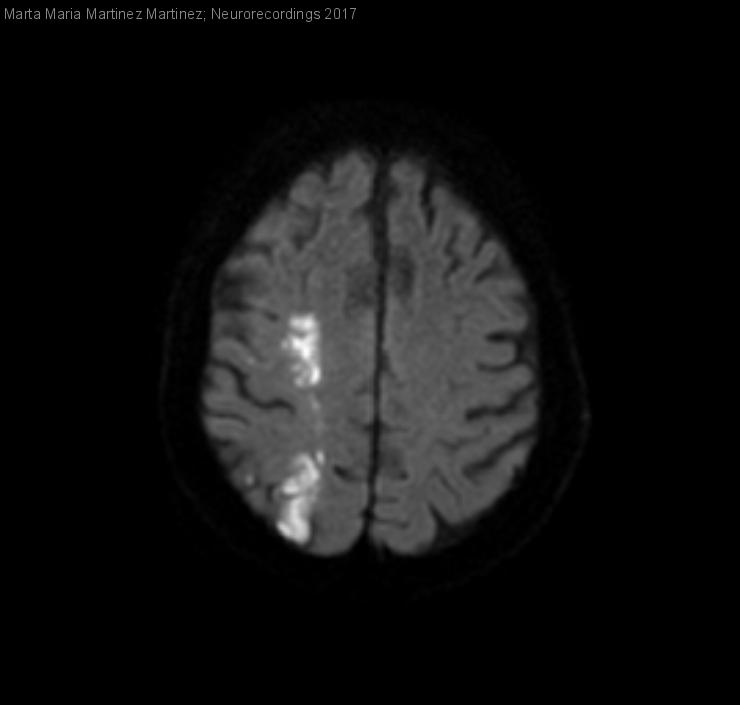

Infarto cerebral en territorios frontera por estenosis crítica de arteria carótida interna derecha.

Diagnóstico final: Ictus isquémico en territorio frontera hemisférico derecho.

Paciente que consulta por pérdida de fuerza y sensibilidad en miembro superior izquierdo. Antecedentes:diabetes mellitus, dislipemia, amputación transmetatarsiana de pie derecho e infracondílea izquierda por infección. En tratamiento con antidiabéticos orales, hipòlipemiante y AAS.